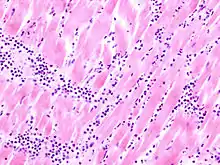

Virale Myokarditis

Ät.: Coxsackie-, ECHO-, Adenoviren, Influenzaviren

Pathogenese: Herzmuskelnekrose durch Virus und T-Zell-vermittelte Immunreaktion.

Mikro: Interstitielles lymphozytäres Infiltrat (kleine blaue Zellen), kaum Nekrosen.

![]() Virale Myokarditis bei Patient mit plötzlichem kongestiven Herzversagen, Autopsiepräparat, H&E. |

![]() idem. |